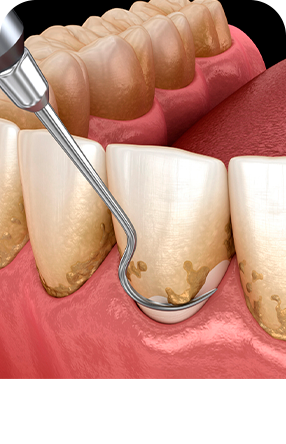

La limpieza dental profesional mejor llamado raspaje y alisado radicular con pulido coronal, se realiza con un equipo llamado ultrasonido el cual emite vibraciones que permiten desprender el sarro o cálculo que se ha ido acumulando en la superficie dental y espacios de difícil acceso para el cepillado dental común.

Incluye:

-Elementos de protección personal

-Educación y motivación en higiene oral

-Ultrasonido casi completo

-Profilaxis

-Desmanchamient